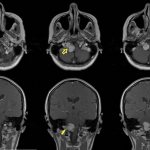

• Магнитно-резонансная, компьютерная томография головного мозга и шейного отдела позвоночника (МРТ и КТ)

• прохождение магнитно-резонансной томографии;

• компьютерная томография;